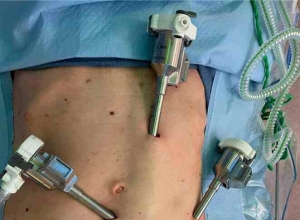

有效、简便、易行的腹腔镜胆囊腹腔镜手术的简易程序Effective, simple, easy procedure for laparoscopic port closure in difficult casesHighlights亮点•The complete fascial closure of port site is esse ...